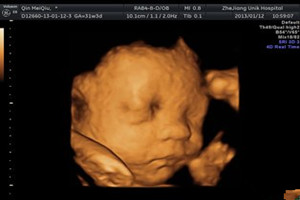

1强大排畸功能,思维彩超的强大排畸功能是目前为所有彩超检查所不能比拟的,它对先天性唇腭裂,肢体畸形、肾脏等器官缺陷效果最佳。

2可以获得胎儿宫内动态图像。更有利于医生判断胎儿发育情况,及时发现异常